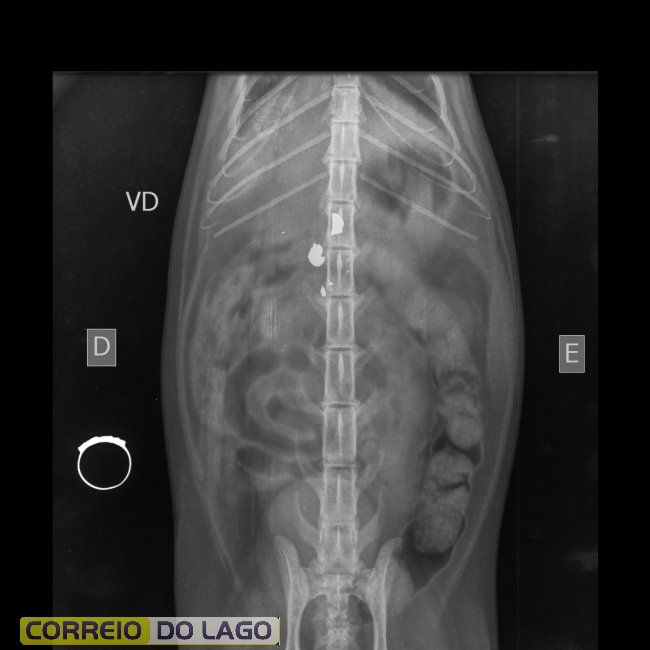

Delegado detalha investigação sobre gata baleada e caso de maus-tratos revolta moradores em Toledo

Conforme o delegado Macorin, o animal já está em atendimento veterinário e deverá passar por cirurgia. O inquérito segue em andamento e o caso poderá se enquadrar na legislação que prevê punições mais severas para crimes de maus-tratos quando praticados contra cães e gatos.